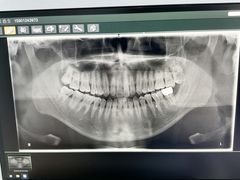

• 永林口腔医院

• -永林口腔医院